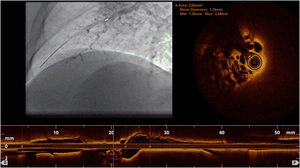

Complementary invasive tools for balloon pulmonary angioplastyContemporary imaging modalities, including intravascular ultrasound (IVUS, Eagle Eye Platinum, Philips, North Ryde, NSW, Australia; Figure 4)17 and optical coherence tomography (OCT, Dragonfly Optis; Abbot Vascular, Santa Clara, CA, USA; Figure 5),19,20 have been applied in BPA for a better characterization of the lesion, its extension and diameter. These imaging modalities are not widely used as they prolong procedure time. Nevertheless, IVUS is particularly useful in determining the vessel diameter in total occlusion BPA (Figure 4), increasing procedure safety.17 Pressure-wire-guided BPA using a microcatheter-based manometer (Navvus rapid exchange FFR micro-Catheter, Acist, Eden Prairie, Minnesota, USA) for distal pressure measurement can be used to guide vessel dilatation and reduce the risk of lung injury in patients with severe baseline hemodynamics (mean PAP>40 mmHg and/or PVR>7 WU).21 In the severe patient subgroup, the dilation of each vessel is stopped before the distal mean PAP (Pd value) reaches 20-25 mmHg,1,2 assessed by pressure wire after each dilation (Figure 6). In previous published data, the optimal cut-off varies between 19.5 to 35 mmHg.22,23 However, since the mean PAP is normally <25 mmHg, this is the cut-off used by our group. In some other cases, the pressure wire could be useful to identify abnormal lesions that are of uncertain significance when assessed by angiography. A Pd/Pa ratio of less than 0.80 could be used to guide treatment.21

Pulmonary balloon angioplasty of a total occluded vessel from a segment of inferior right lower lobe, guided by intravascular ultrasound (IVUS). A) Selective pulmonary angiography showing occlusion of one of the A10 subsegments (red arrow); B and C) IVUS using an Eagle Eye® Platinum ST catheter (Philips, Amsterdam, the Netherlands) enabling the accurate determination the real size of the vessel and, thus, size the balloons to be used during angioplasty; D) Dilatation of the vessel with a 4.0-mm diameter balloon; E) Selective pulmonary angiography showing a good final result of chronic total occlusion (CTO) balloon plastic angioplasty (BPA) (red arrow). There is another CTO in segment A9 (yellow arrow) that was proposed to intervene later; F) Two months later, the final angiography revealed good BPA result in the previous CTO intervention and A9 CTO lesion successfully treated.

Pressure-wire-guided balloon plastic angioplasty of right medium lobe A5 segment, measuring distal pressure using a microcatheter-based manometer (Navvus rapid exchange FFR micro-Catheter, Acist, Eden Prairie, Minnesota, USA). This was the first session of a severe chronic thromboembolic pulmonary hypertension patient with systolic pulmonary artery pressure (PAP) around 80mmHg and mean PAP 40 to 50 mmHg. A) Subocclusion of two A5 subsegments in selective angiography. Intravascular hemodynamics (bottom left) revealed a significantly dampened distal pressure waveform (green line) and resting Pd/Pa=0.21; B) Improved angiographic appearance of one A5 subsegment after successive dilation with 2.0-mm and 3.0-mm balloons. Intravascular hemodynamics (bottom right) revealed improved distal pressure waveform with a Pd value of 22mmHg (green line); C) Final angiographic result with improved vessel perfusion in both subsegments.